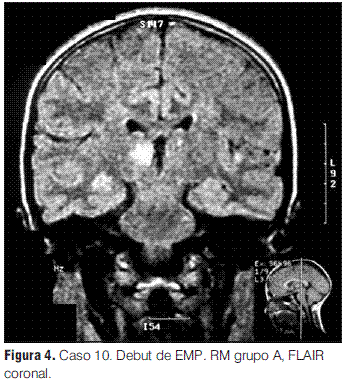

En nuestra serie no se presentaron recaídas ni recurrencias, con una media de tiempo de seguimiento de 3 años y 1 mes. Sin embargo, de los 12 pacientes con diagnóstico inicial de EMDA incluidos en este estudio, uno evolucionó a una esclerosis múltiple pediátrica (EMP), de acuerdo con los criterios propuestos por el consenso de expertos del “International Pediatric MS Study Group”, representando el 0,09 de la población en la que se pudo realizar seguimiento; la proporción de pacientes que tienen esta evolución varía en las diferentes series entre el 9% y el 40% (2,3); la presentación inicial de esta paciente con clínica polisintomática y con compromiso de conciencia (sintomatología EMDA-like) es una forma frecuente de debut de la EMP, lo cual subraya la importancia del seguimiento clínico e imagenológico sistematizado y prolongado para poder llegar a un diagnóstico definitivo [comunicación personal Tenembaun y colaboradores (33)]. Destacamos la afectación de los PEV sin repercusión clínica en este paciente, como signo de lesiones desmielinizantes silentes (4,2,17,27,28,34,35).

En cuanto a las RM de control, siete se normalizaron entre el año y los 3 años 7 meses; las cuatro en las que persistieron lesiones correspondieron tres de ellas a los pacientes con secuelas (tanto motoras como epilepsia secundaria y nivel cognitivo descendido) y una a un paciente que evolucionó a la esclerosis múltiple pediátrica (EMP) (tabla 3).

La mayoría de los EEG mostraron enlentecimiento de la actividad de fondo y descargas epileptiformes, hallazgos inespecíficos en relación a esta patología, como está descrito en otras series (2,4). Los PEV mostraron alteraciones en el paciente que evolucionó a la EMP, lo cual apoyaría la utilidad de los estudios electrofisiológicos en la detección de lesiones desmielinizantes asintomáticas frecuentes en niños con EMP (2,26,27). Los PEAT fueron normales en los dos pacientes evaluados con esta técnica.